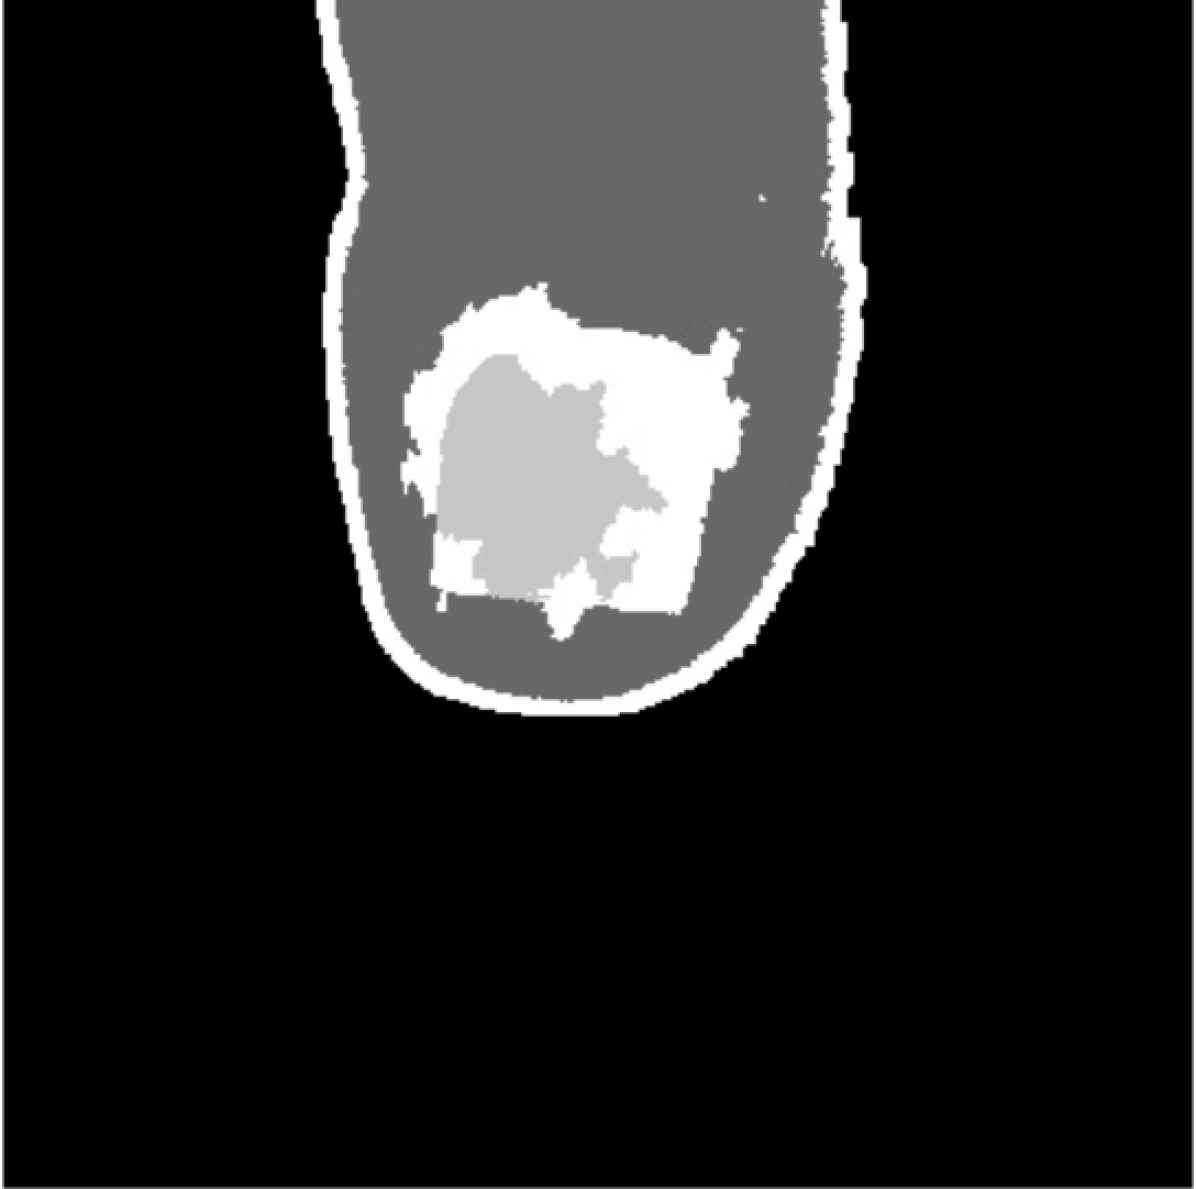

To group close and similar pixels we use the Quickshift algorithm Vedaldi and Soatto (2008). It divides the image in connected and uniform regions, the so-called super-pixels. However, as can be seen in Fig. 6, a set of connected super-pixels define the nail contour accurately.

The watershed segmentation algorithm requires the definition of initial markers that grow until they fill a whole region. To initialize the algorithm, we use the probabilities of each super-pixel to belong to a class, given by the gradient boosting classifier. More specifically, we initialize some super-pixels as watershed initial markers as follows:

-

•

Marked as background. Super-pixels on the excluded region of the foot ROI mask, slightly eroded with kernel.

-

•

Marked as nail. Super-pixels whose estimated probability of being part of the nail is greater than 99.99%, to guarantee as much as possible the correctness of the initial marker.

-

•

Marked as skin. Super-pixels with a probability greater than 99.99% of being skin.

-

•

Unmarked. The rest of pixels are tagged by the watershed algorithm based on their closeness and similarity to the already marked pixels.

In Fig. 7(a), we can appreciate that the contours of the nail are sharp. Thus, provided the initial markers are corrected, the growth of the nail and skin regions would be prone to stop at these edges. This has been actually the case when processing images in practice, as shown in Fig. 7(d).